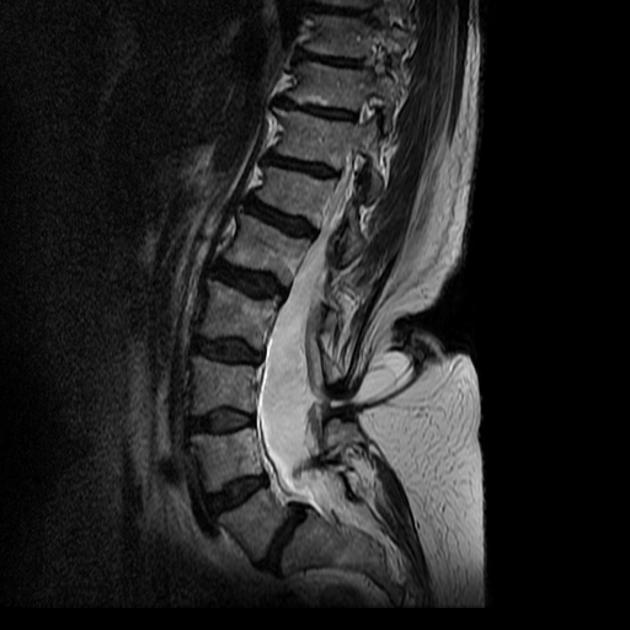

Эффективный и при этом весьма безопасный для организма малыша способ диагностики спины Бифида — МРТ. На сделанных послойно фото можно подробно рассмотреть все дефекты и убедиться в диагнозе.

У младенцев после рождения и у взрослых основной метод диагностики — рентгенография позвоночного столба. Метод позволяет оценить степень незаращения дужек и выход спинного мозга в образовавшуюся щель.

Из дополнительных методов возможно применение трансиллюминации, основная цель которой — точно определить содержимое мешка. Для оценки степени недоразвитости и повреждения спинного мозга показана контрастная миелография.